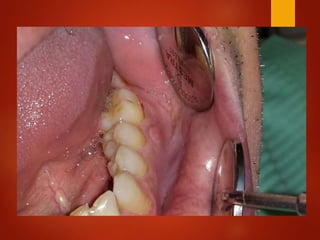

El documento es un registro médico odontológico que muestra las fechas de las visitas de un paciente al centro de salud El Raval, incluyendo exámenes y tratamientos realizados como la extracción de cálculos salivales en abril y mayo de 2012.